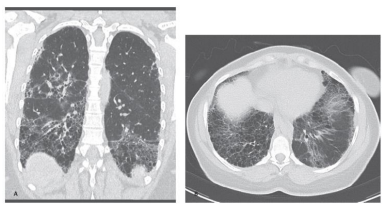

Certo paciente compareceu ao hospital apresentando

dispneia durante exercícios há 5 anos. Assinalar a alternativa

que se refere à categorização CORRETA da tomografia

computadorizada de doença pulmonar fibrótica para esse

paciente: